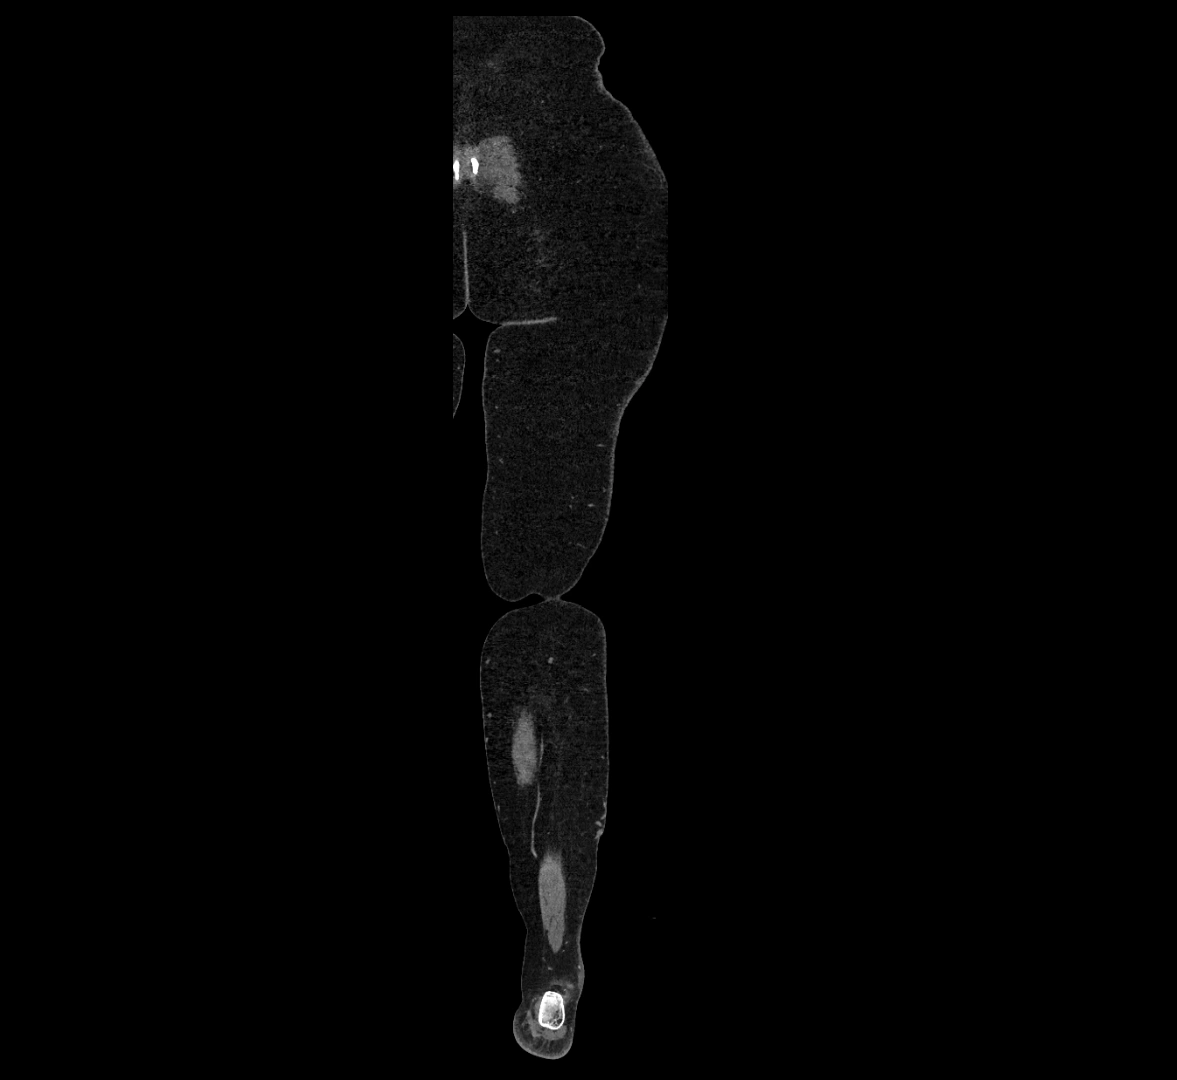

MRI images

image